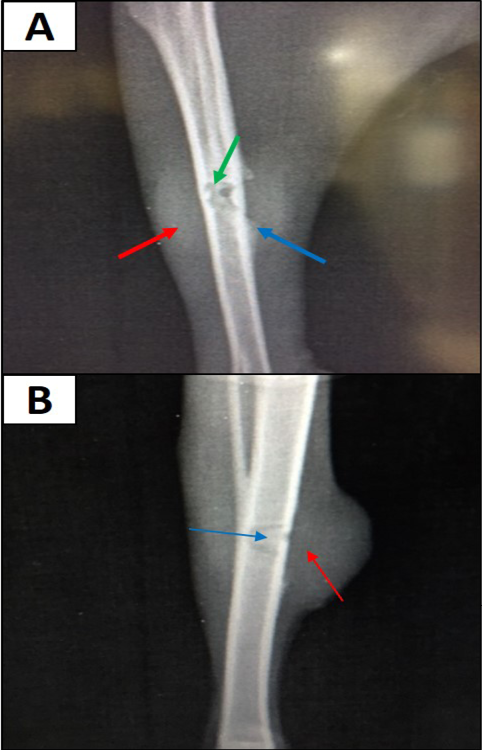

Site of operation, 7 days post treatment with Staph specific – bacteriophage given intramuscularly (Group C), all features of osteomyelitis disappeared, almost clear medullary canal (→), uniformed bone density and cortex returned to normal thickness (→), but the hole still exists (→) (ML View)

Site of operation, 7 days post treatment with Ceftaroline given intramuscularly (group D): A) Chronic Osteomyelitis (Seqeustrum still exists) (→) (ML View); B) Radiopaque area in soft tissue present represent accumulated pus (→) (AP View)